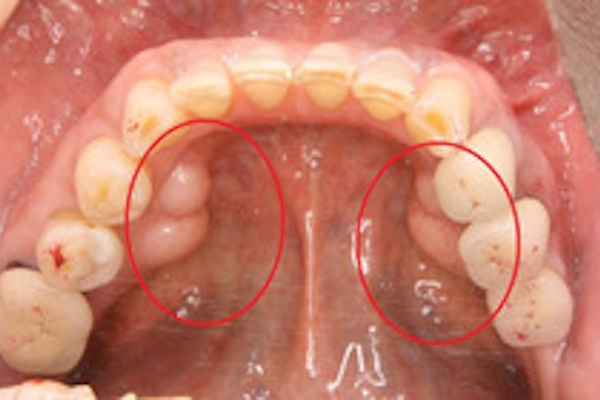

骨隆起(こつりゅうき)/外骨症(がいこつしょう)

食いしばりや歯ぎしりが強い方に多く見られる症状で、顎の骨に過度の力が加わり、その刺激によって骨が盛り上がってできると言われております。

骨隆起は痛みを伴うものではなく、また病的なものでもありませんので放置していても問題はありませんが、徐々に大きくなっていきますので、発音や飲食に支障が出るようでしたら切除する必要があります。